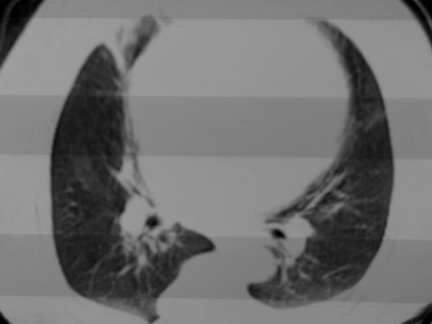

标题: CT13142:女 80 胸闷、气短、1w [打印本页]

标题: CT13142:女 80 胸闷、气短、1w

右肺炎性变,双侧甲状腺肿,胸膜肥厚。

右肺炎性变

双侧胸腔积液

缩窄性心包炎

左室为主的心脏增大。

胸膜肥厚,

气管,支气管软骨钙化。

右肺感染;双侧胸腔少量积液,心影增大,可能与心功不全有关;胸内甲状腺肿。

右肺炎性变,双侧甲状腺肿,胸膜肥厚,心影增大考虑心功能不全.

胸内甲状腺肿;右肺感染;双侧胸腔少量积液。

胸内甲状腺肿;右肺中叶感染;双侧胸腔少量积液;心影增大,考虑有心功能不全。